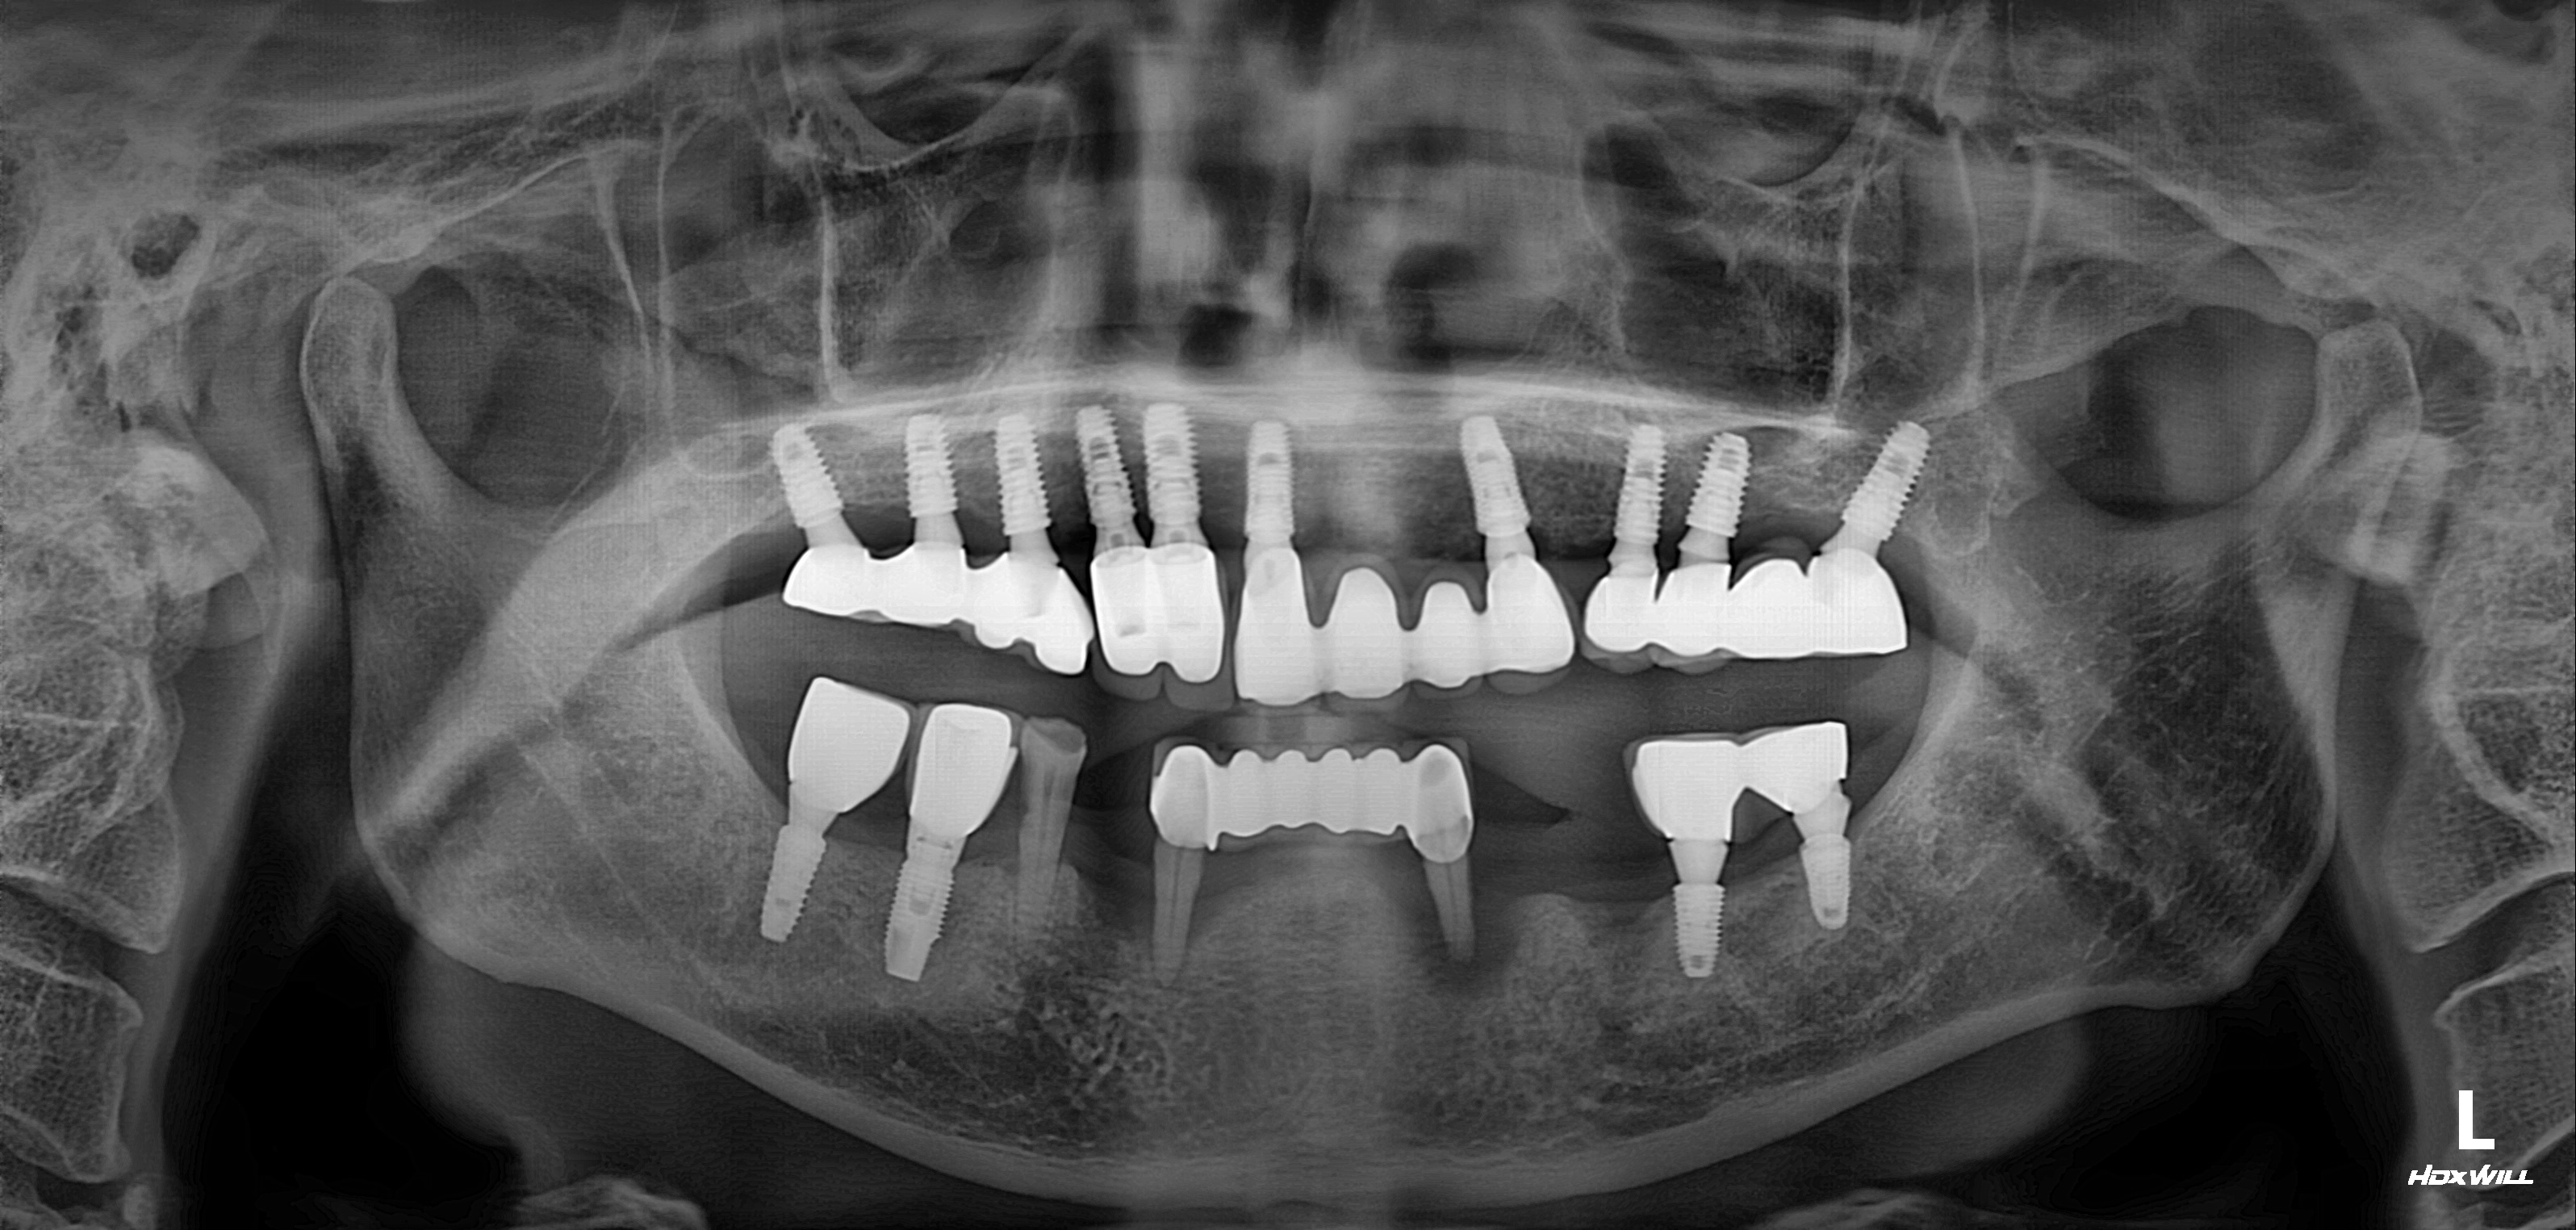

수술 전

수술 후

전악임플란트 식립사례

전후사진